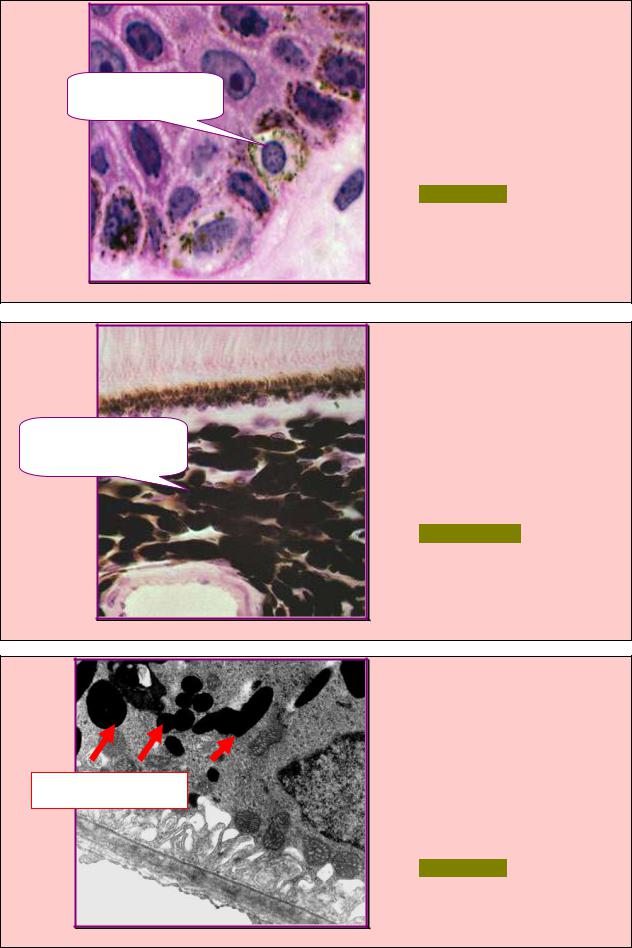

В препарате эпидермиса кожи |

выявили |

отростчатую |

клетку |

Синтезирует пигмент |

нейронального |

происхождения |

меланин |

(стрелка), |

функция которой представлена |

на рис.4.102. Назовите данную |

клетку. |

А. Ретикулярная. |

Б. Меланоцит. |

В. Интердигитирующая. |

Г. Меланофор. |

Д. Дендритная. |

Рис. 4.102 |

ЗАДАНИЕ 4.103 |

В |

препарате |

стенки |

глаза |

выявили соединительнотканные |

клетки (стрелки), специфи- |

Захватывают путем |

ческая |

функция |

которых |

представлена |

рис.4.103. |

эндоцитоза гранулы с |

Назовите данные клетки. |

меланином |

А. Ретикулярные. |

Б. Меланоциты. |

В. Интердигитирующие. |

Г. Меланофоры. |

Д. Дендритные. |

Рис. 4.103 |

ЗАДАНИЕ 4.104 |

При электронной микроскопии |

эпидермиса |

кожи |

соедини- |

тельнотканную |

Меланосомы |

специфические |

||

структуры |

которой |

лены на рис.4.104. Назовите |

данную клетку. |

Рис. 4.104 |